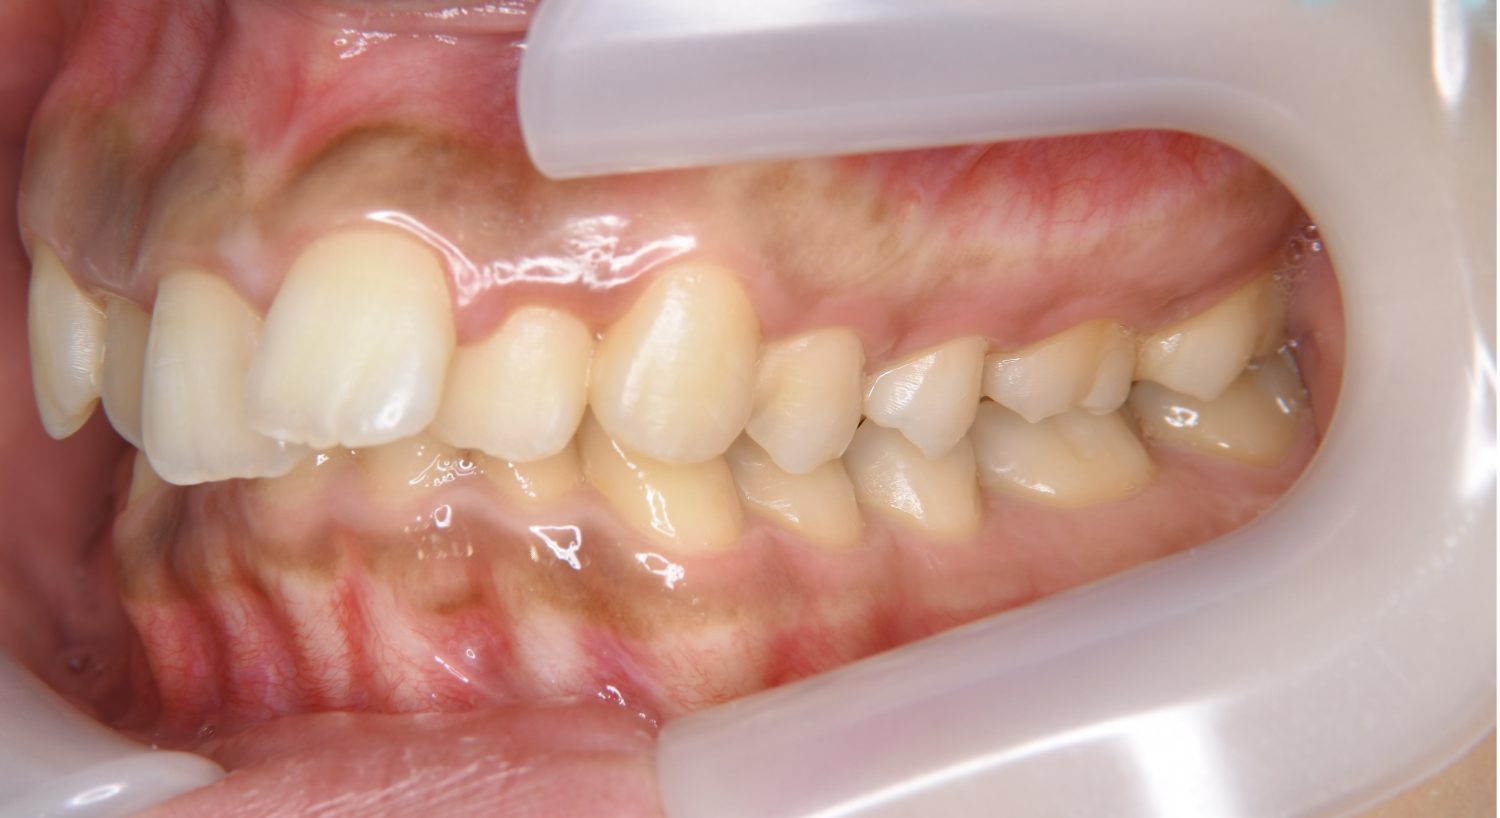

叢生の症例紹介②

Before

After

主訴

歯の凸凹を治したい。

治療内容

アライナー(インビザライン)にて非抜歯で治療を行いました。

治療費

1,150,000 円(税込)

治療期間

26ヶ月

通院回数

14回

想定されたリスク

※歯根吸収、歯肉退縮、歯髄壊死、顎関節症状

※アライナー(インビザライン)は日本の薬機法未承認の矯正装置であり、医薬品副作用被害救済制度の対象外となる場合があります。

丸山和宏先生

ピーススマイル矯正歯科

上下前歯部に叢生(凸凹)が認められる状態でした。歯列の遠心移動を行うことで機能面および審美面が改善されました。